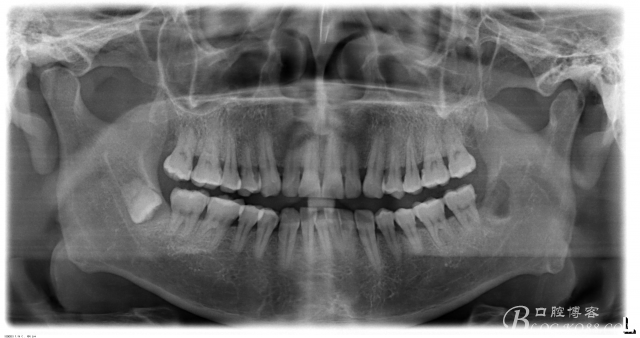

一、術(shù)前CBCT影像資料

下頜倒置阻生智齒的拔除

李某某、男、46歲。主訴:左側(cè)張口困難伴下唇麻木一周?,F(xiàn)病史:一月前,患者自覺左側(cè)下頜后牙牙齦腫痛,抗炎治療效果不佳,近一周出現(xiàn)張口困難,同時(shí)伴有左側(cè)下唇麻木。遂來(lái)我院就診。

口內(nèi):38未萌出。37遠(yuǎn)中牙周袋10mm,CT:38牙冠倒置。牙齦紅腫,捫診可有少量血性滲出,無(wú)波動(dòng)感。印象診斷:38冠周炎。處理:1.抗炎治療,改善張口度。2.炎癥消退后,拔除38.